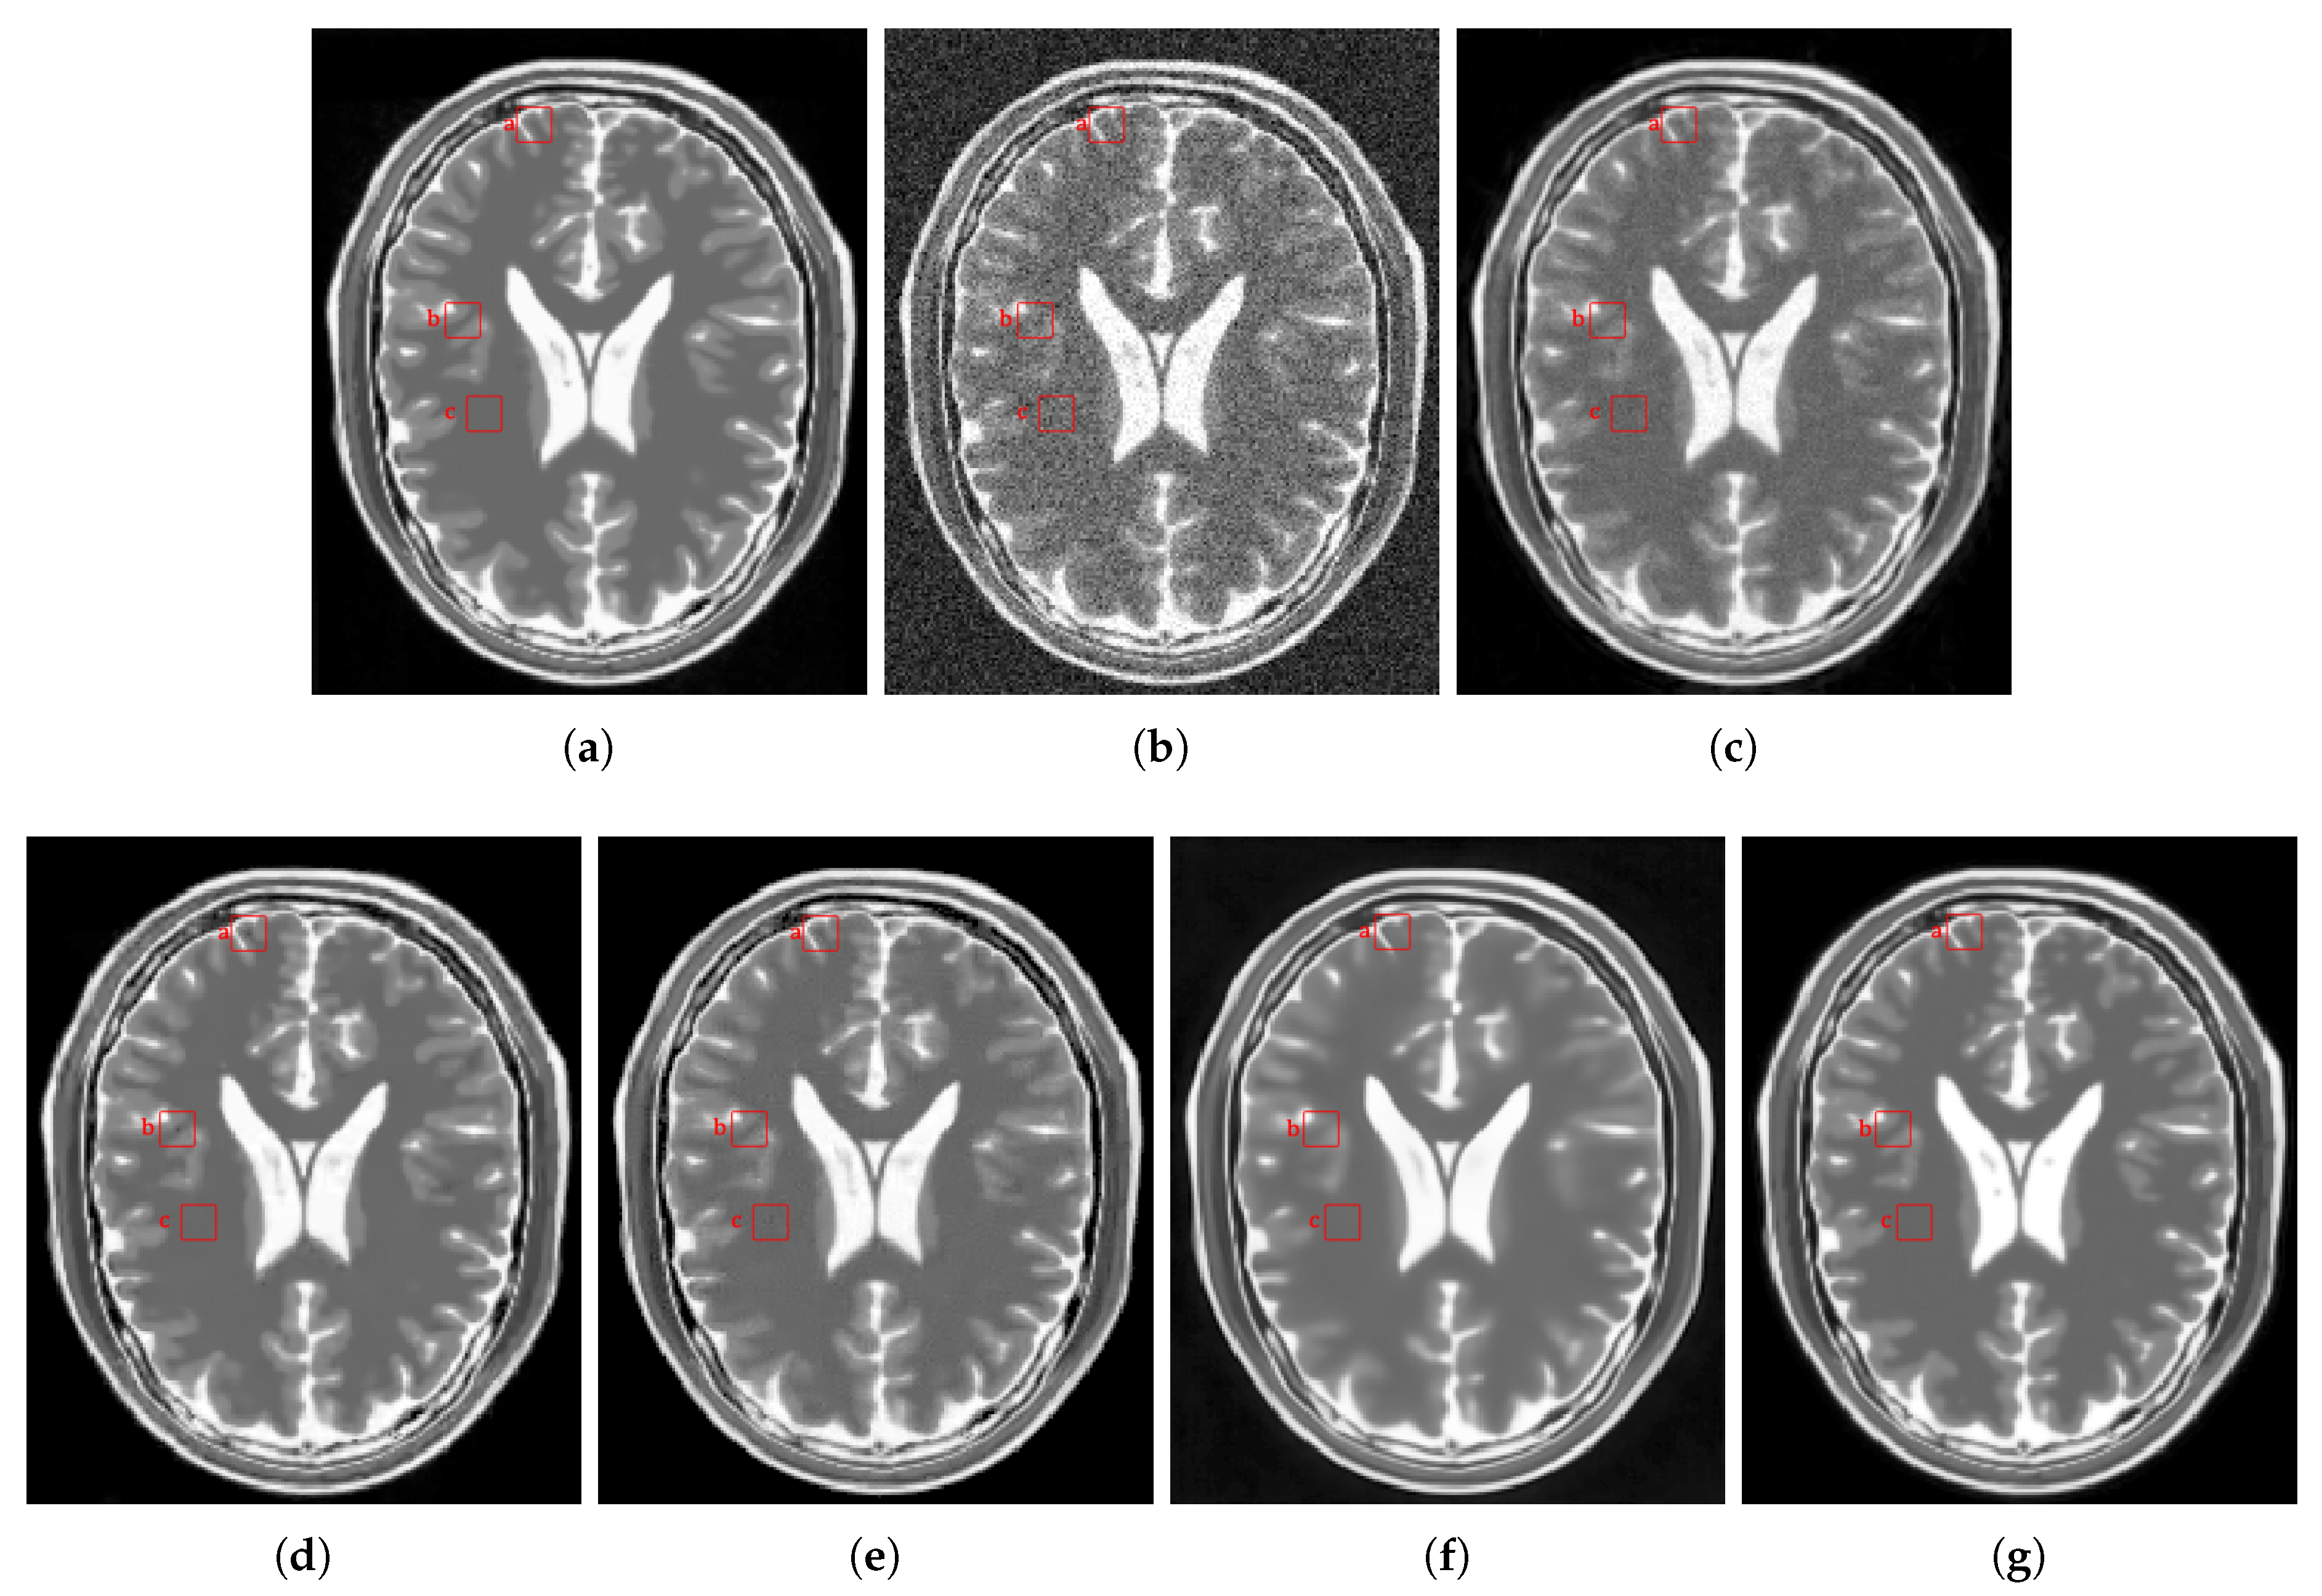

4.2.1. Synthetic Data

4.2.2. Real Data